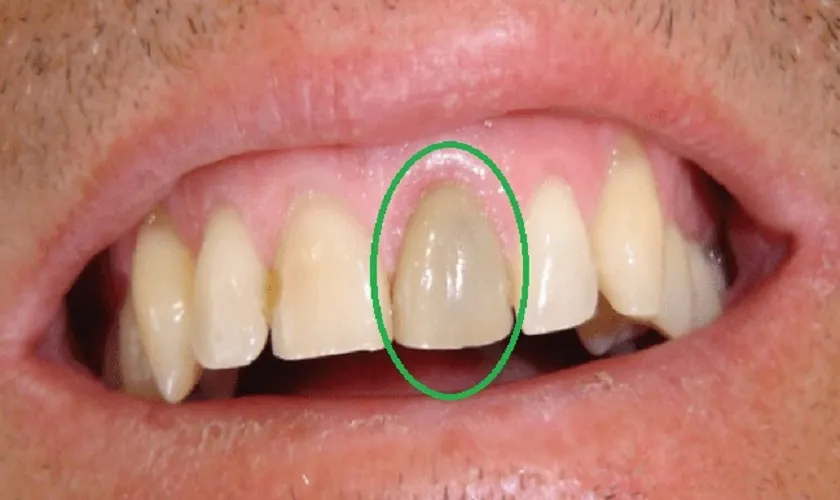

Chấn thương (cơ học, nhiệt độ…) khiến răng bạn không ngừng đau buốt, lúc đó răng cần được điều trị tuỷ răng.

Nếu phát hiện hay nghi ngờ có răng cần phải điều trị tuỷ, bác sĩ sẽ chỉ định chụp phim thêm tại vùng răng đó. Mục đích để đánh giá chính xác hơn mức độ tổn thương và độ khó của răng cần chữa tuỷ.